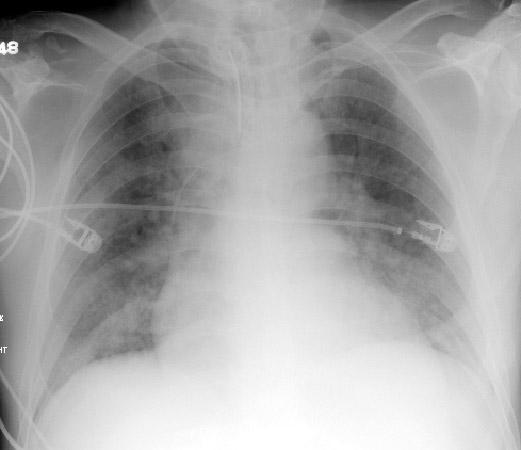

KKY görülen bulgular;

2- Kardiyomegali (kardiyo-torasik oran > %50)

3- İnterstistal ödem

4- Genişlemiş pulmoner arter

5- Plevral efüzyon

6- Alveoler Ödem

7- Belirgin SVC

8- Kerley çizgileri B

9-Peri-bronşiyal kanlanma

10-İnterlobar fissürlerin kalınlaşması

11-Yarasa dağılımı